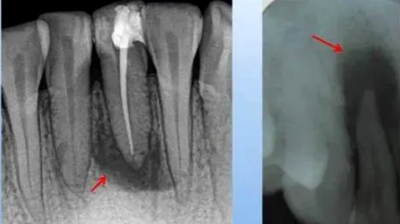

2.急性化膿性根尖周炎

病理及臨床:牙周膜滲出物增多,白細(xì)胞壞死溶解形成膿液。癥狀明顯,有自發(fā)性、持續(xù)性搏動(dòng)性疼痛,叩痛明顯。

X線表現(xiàn):根尖部不規(guī)則,小區(qū)域的透射影,邊界不整齊,范圍局限。